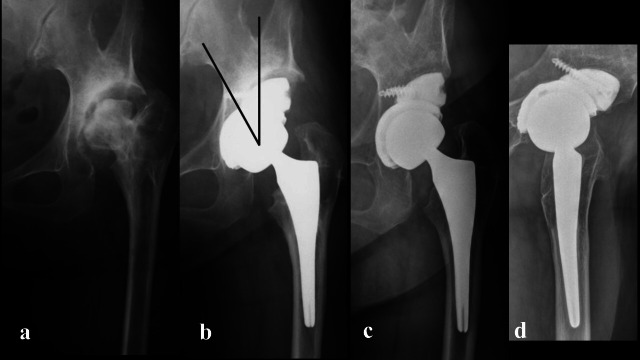

Aims: This study aimed to evaluate the efficacy of porous titanium acetabular augments in primary total hip arthroplasty (THA) for reconstruction of superolateral acetabular bone defects in patients with Crowe II or higher classes of developmental dysplasia of the hip (DDH) or rapidly destructive coxopathy (RDC).

Methods: We conducted a retrospective evaluation of 27 patients (30 hips) who underwent primary THA using cementless cups and porous titanium acetabular augments. The follow-up periods ranged from two to 11 years, with a mean of 5.0 years. The cohort included 22 females (24 hips) and five males (six hips), with a mean age of 67 years (45 to 83) at the time of surgery.

Results: At the final follow-up, there was no radiological evidence of loosening or radiolucency around the cups and augments, indicating successful biological fixation in all cases. Clinically, there was a significant improvement in the Western Ontario and McMaster Universities Osteoarthritis Index score, which improved from a mean of 39.1 (SD 14.7) preoperatively to 5.1 (SD 6.4) postoperatively.

Conclusion: The use of cementless cups and porous acetabular titanium augments in primary THA for patients with DDH and RDC can lead to considerable clinical improvements and reliable biological fixation, suggesting their potential as a viable solution for managing challenging acetabular defects in these conditions.